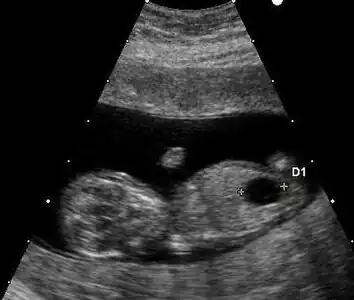

Ultrasound

Ultrasound imaging can be used to screen for Down syndrome. Findings that indicate increased risk when seen at 14 to 24 weeks of gestation include a small or no nasal bone, large ventricles, nuchal fold thickness, and an abnormal right subclavian artery, among others.[89] The presence or absence of many markers is more accurate.[89] Increased fetal nuchal translucency (NT) indicates an increased risk of Down syndrome picking up 75–80% of cases and being falsely positive in 6%.[90]

Ultrasound of fetus with Down syndrome showing a large bladder

Enlarged NT and absent nasal bone in a fetus at 11 weeks with Down syndrome